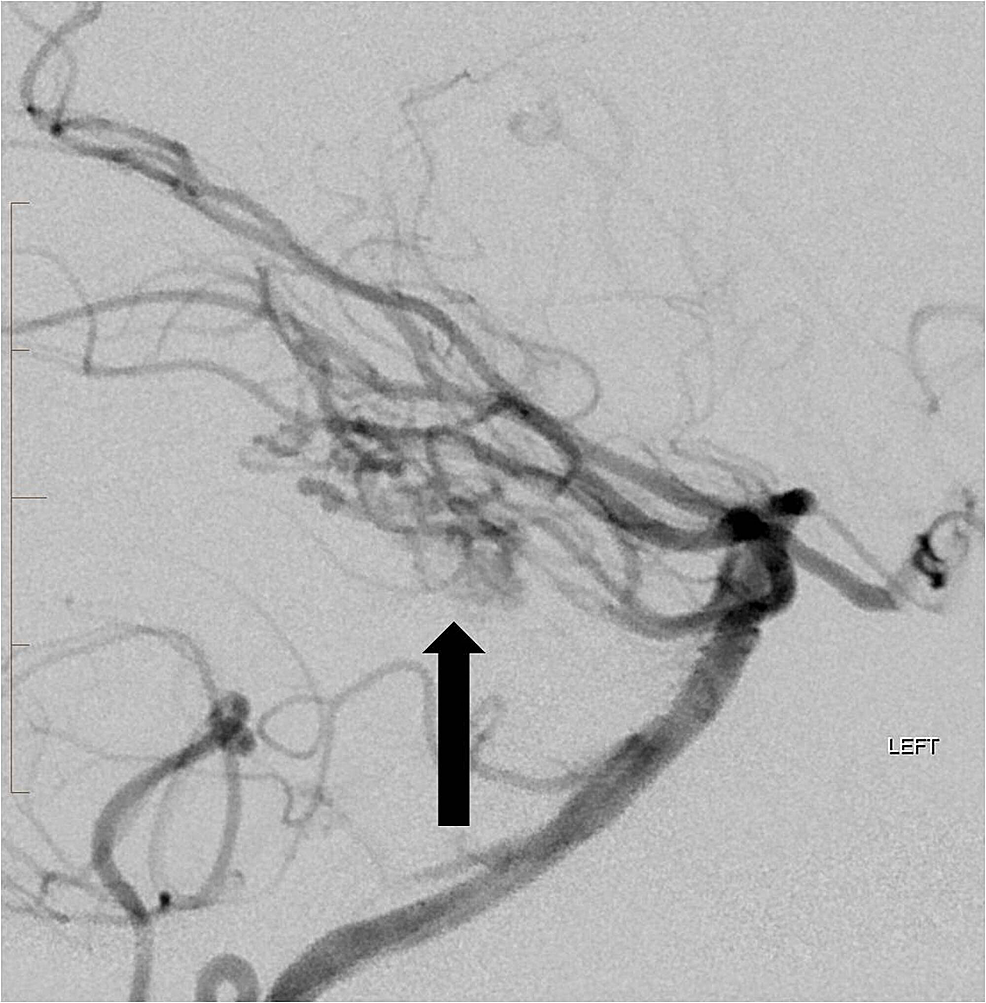

She was scheduled for pre-operative embolization and surgery the following week. Under general anesthesia, a 5-French catheter was advanced into the left vertebral artery where digital subtraction angiography (DSA) was performed. Over a microwire, a microcatheter was then advanced into the left superior and anterior inferior cerebellar arteries near the nidus of the AVM. A mixture of 250-355 micron PVA particles was then injected carefully under fluoroscopic observation until there was visible slowing of antegrade flow in each of the branches. Approximately 75% reduction in volume of the AVM was achieved and there was a marked reduction in the flow dynamics (Figure 9).